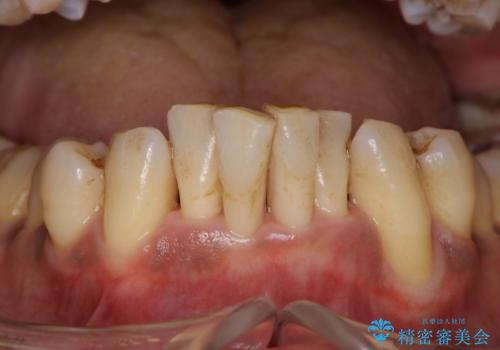

黒々とした厚みのある歯石が歯の表面に沢山付いていました。

まず、歯石除去を5回に分けて歯茎の下に付いている歯石をとりながら(麻酔あり)ホームケアの大切さ

ブラッシング指導を行っていきました。